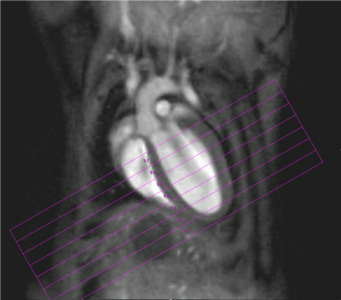

Physiological gating is required to minimize motional influence of the beating heart and respiration on the MR experiment but also to synchronize the imaging sequence to the cardiac cycle. Beside ECG electrodes and wires, a respiration sensor as well as tubings for inhalation and anaesthesia have to be kept within the probe head. In all measurements body temperature of the examined animal has to be maintained via thermostatically regulated water flow system. Currently it is possible to carry out all experiments necessary for the determination of the functional parameters of rat or mouse ventricles, like end-diastolic, end-systolic, and stroke volumes, ejection fraction, cardiac output, ventricular mass and wall-thickness within less than 45 minutes (Fig. 2).

Fig. 2: Mouse heart MRI. In the upper panel the endsystolic (a) and enddiastolic (b) phase of a mouse heart in the 4-chamber-view is displayed. In red: position of the 7 slices, orthogonal to the septum (1.0 mm thick, no gap). In the lower panel in (c) the endsystolic and in (d) the enddiastolic phase of an axial midventricular slice is shown. Note the papillary muscle.